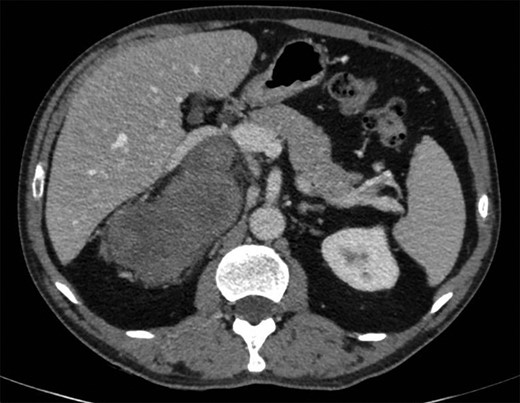

The magnetic resonance imaging (MRI) found the mass, which was measured at 85 × 60 × 160 mm, heterogeneous, with isointense and T1-weighted hyposignal (Fig. 2), isointense and T2-weighted hypersignal (Figs 3 and 4), and diffusion-weighted heterogeneous hypersignal. After injection of the contrast product, the mass did not appear to be hypervascular, and uptake was more pronounced in the late phase, indicative of a fibrous nature. The FDG-PET scan showed a hypermetabolic mass with SUVmax of 6.3. Finally, after excess secretion of catecholamines had been ruled out, a CT-guided biopsy was performed, with the histological analysis concluding that a schwannoma was highly probable.